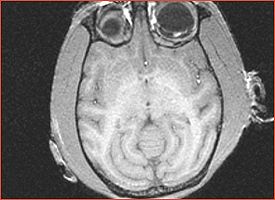

Angio sequence (right name?) has apparently been used for some (7 out of 10) subjects CLW: This is normal T1w blood flow artifact, but it is pronounced, perhaps because of the small brain size.

Fat shift artifact significantly obstructs the cortex in the occipital lobe for all subjects